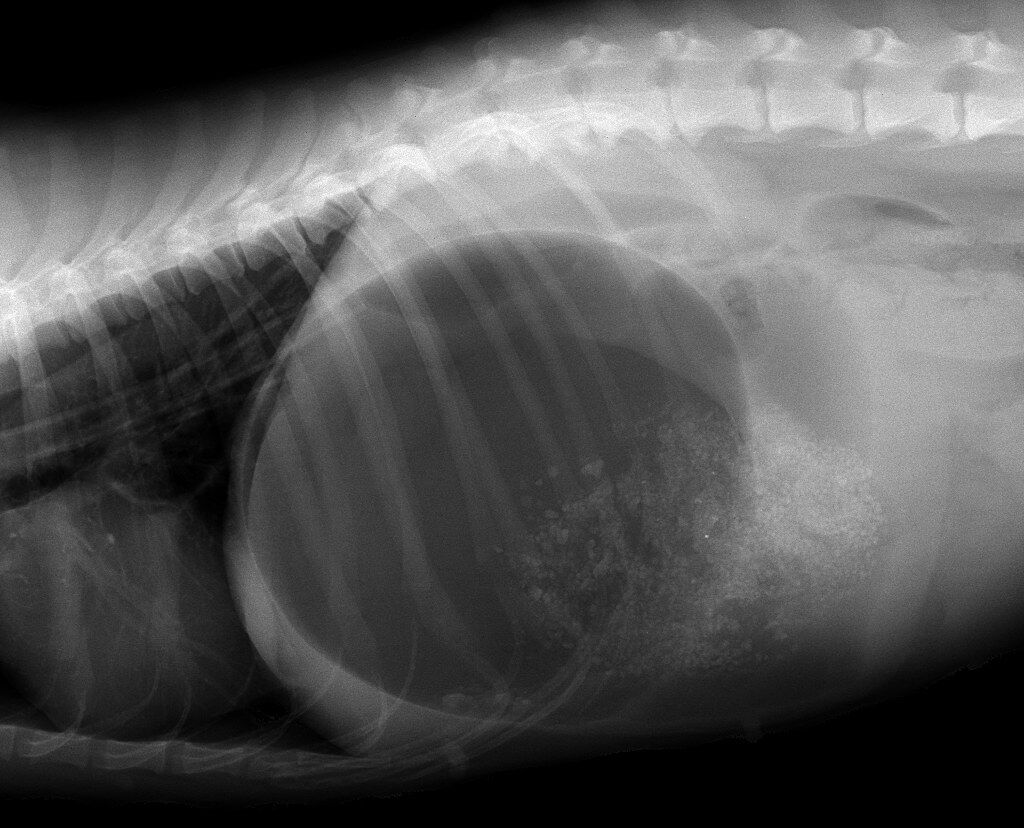

犬の胃拡張・胃捻転症候群 胃拡張とは、ガス・液体・食べたものによって胃がパンパンに膨らむことです。 拡張した胃がねじれた状態を胃捻転と言います。 胃拡張・胃捻転になるとご飯の後に元気がなくなり、お腹が張って苦しそうになります。 涎を垂らしたり、嘔吐したりすることもあります。 重度では血管が圧迫され、臓器の血流が障害されるため お腹 の中で膿が 胃拡張・胃捻転 胃拡張・胃捻転症候群は、食後の胃内にガスが大量発生し、膨れ上がった胃が捻転(ねじれ)を起こすもの。お腹が膨れる、吐こうとしても吐けない、荒い息をするなどの症状がみられ、緊急処置が必要な病気です。 水のがぶ飲みや食後の激しい運動 よく見るとお腹がパンパンに張っています。 『去年のようにまた胃拡張をおこしたか?』と思い急いでレントゲン写真を撮りました。 出来上がったレントゲンを見てみると・・・・ 青褪めました・・・胃拡張じゃない。胃捻転を起こしているかもしれない・・・ これは昨年の胃拡張のレ

ペット豆知識no 18 腹囲膨満 お腹パンパンそれ肥満 胃拡張 胃捻転症候群による腹囲膨満のシェパード 本症例は警察犬 で炎天下の捜査後に食餌をし 数時間してぐったりの状態で来院 麻酔下で胃にチューブを挿入してガスを抜き 同時に胃洗浄も実施 正しく救急疾患